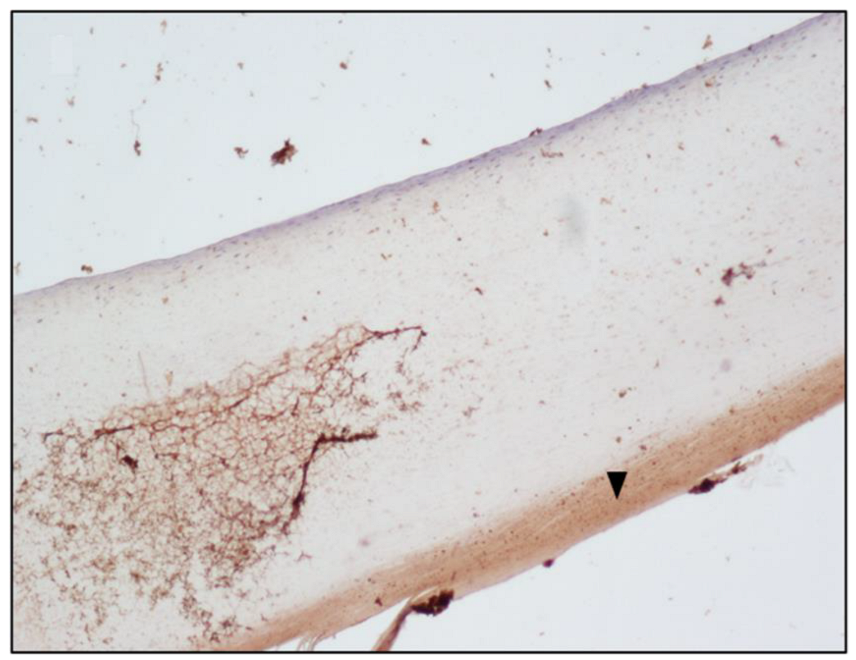

| Fingernail matrix | Area | Mean |

| Subject A (Figure 1) | 1,228,800 | 19.695 |

| Subject A matrix | Instrument | Morphine | 6-MAM | Codeine | Methadone | EDDP |

| Blood | GC-MS | 472 ng/ml | Negative | Positive | Positive | Positive |

| Scalp hair | UHPLC | 3.64 ng/mg | 1.42 ng/mg | Positive | Positive | Positive |

| Fingernail | UHPLC | 0.35 ng/mg | 0.43 ng/mg | Positive | Positive | Positive |